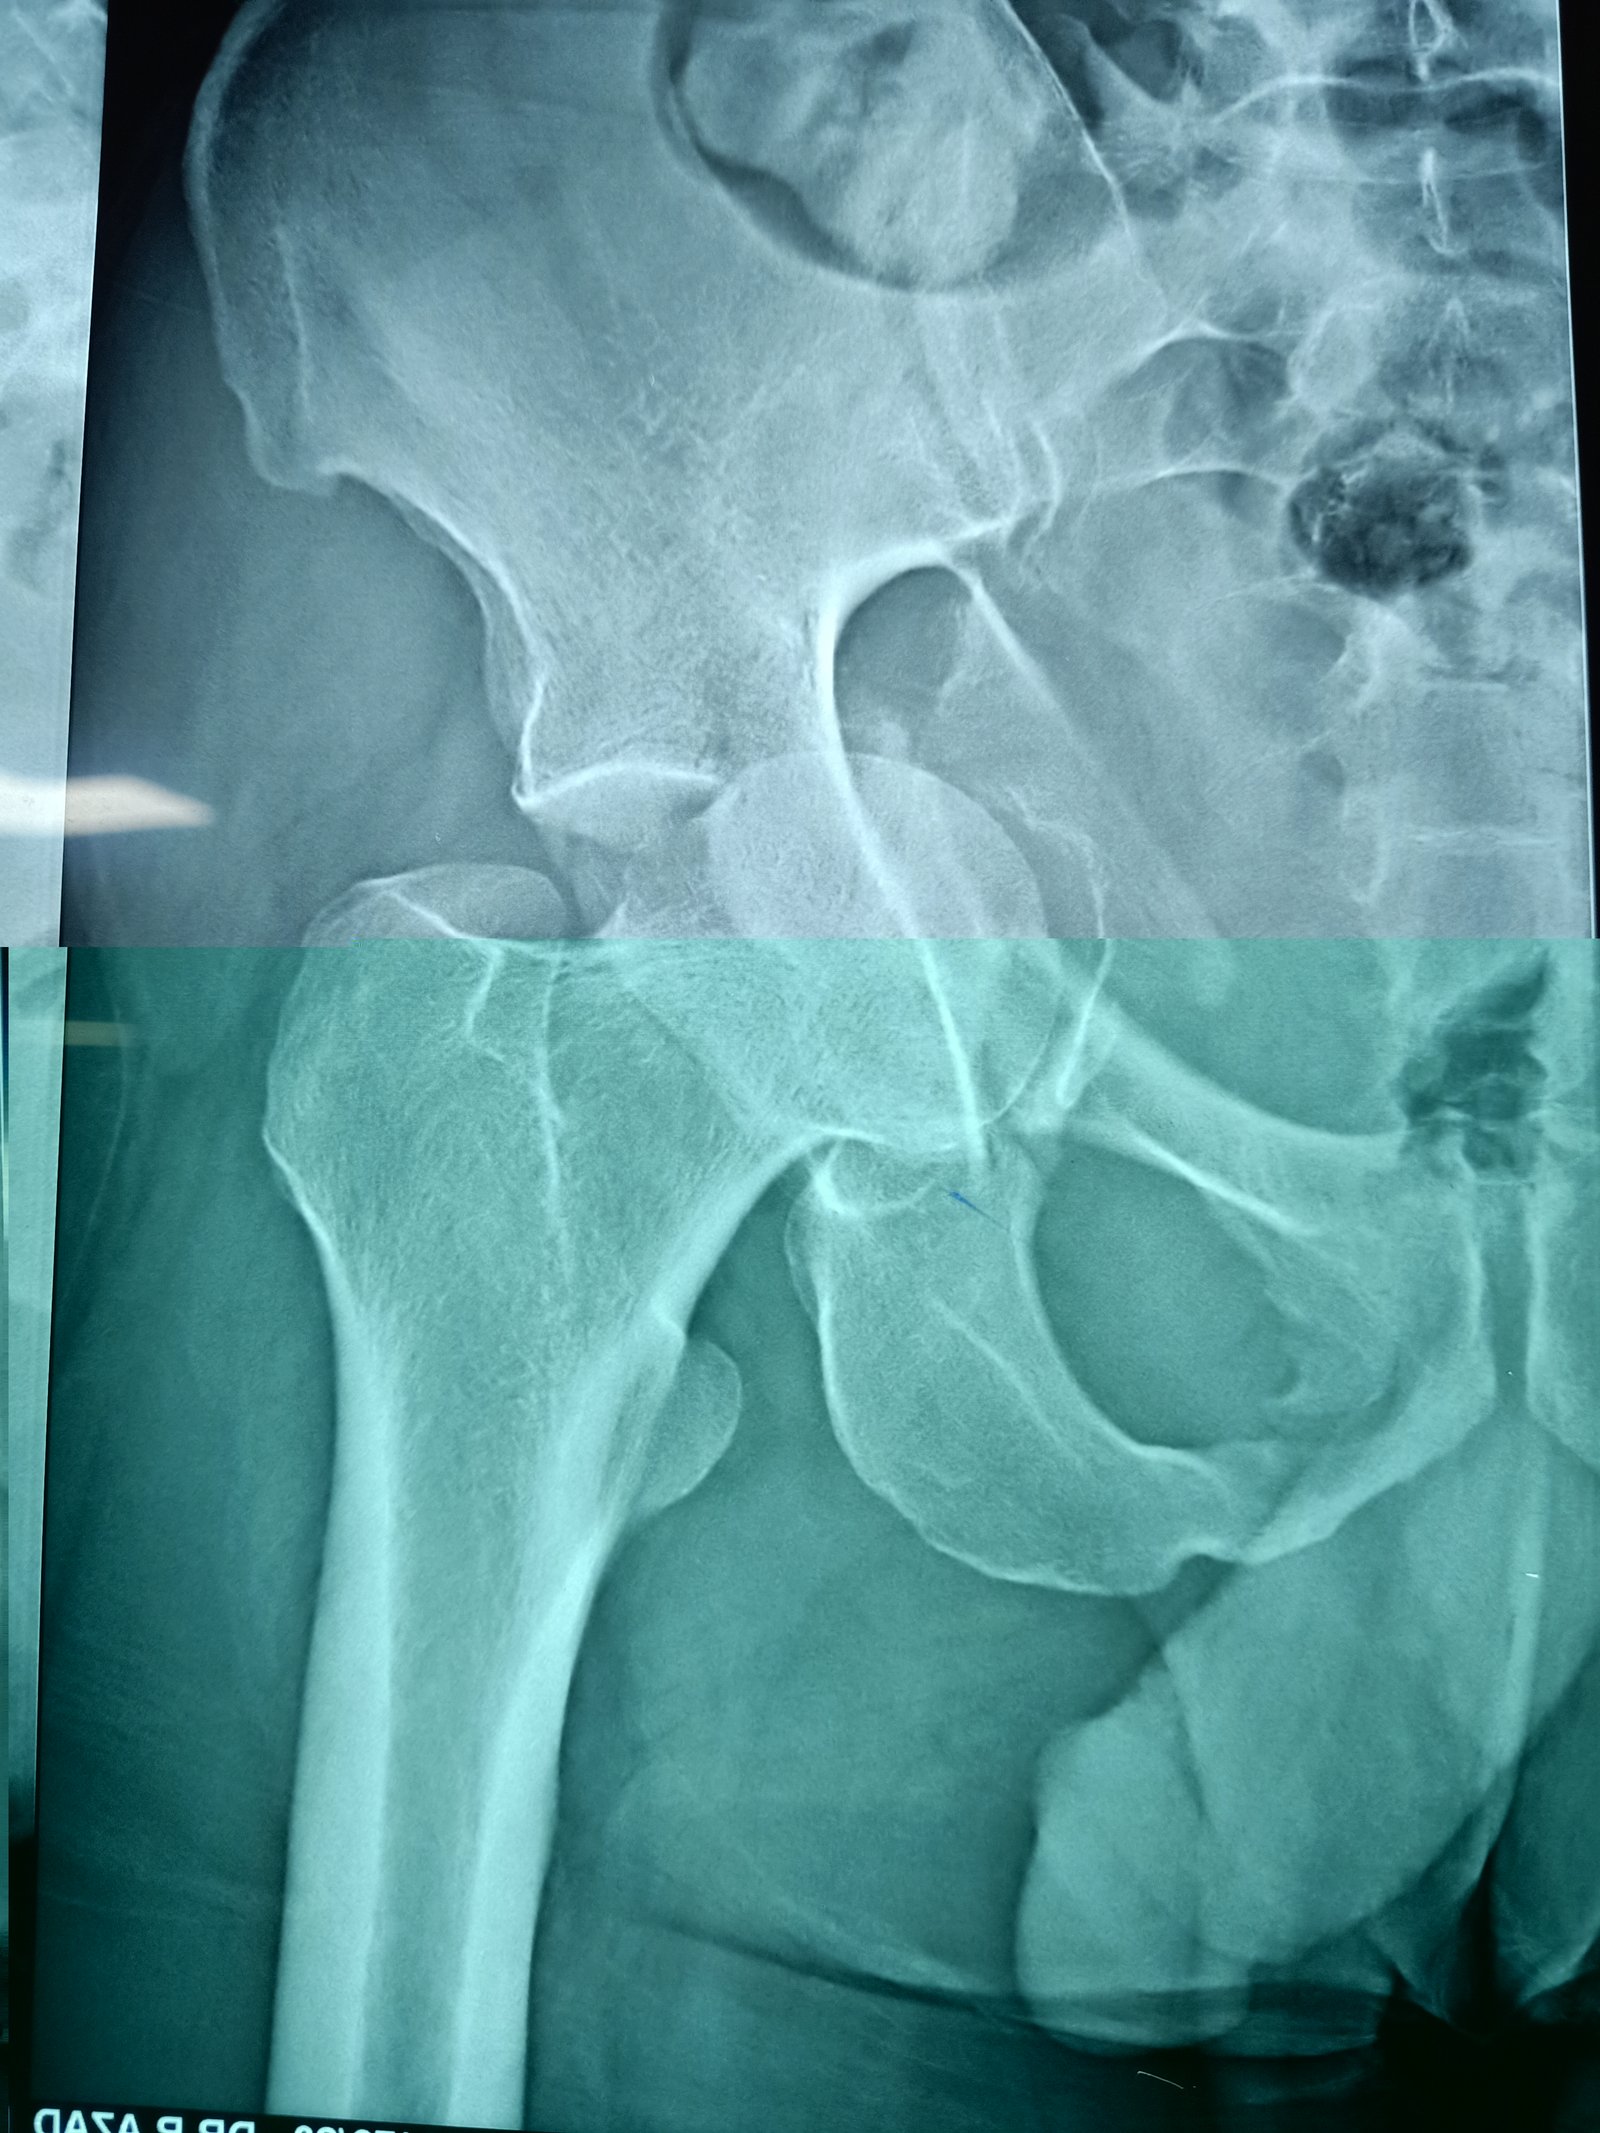

acetabulum

anterior collumn of acetabulum fixation done via anetrior appoach